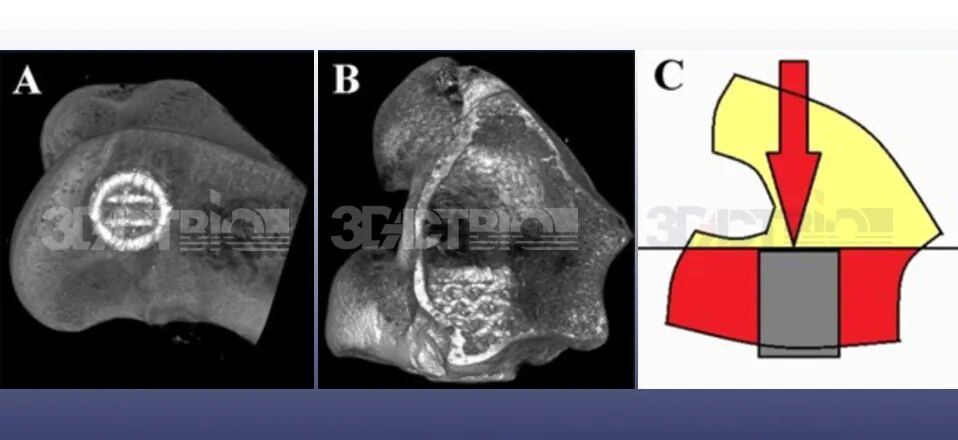

经Bio处理产生的微孔形貌对于提高骨/种植体界面的粘合强度起着至关重要的作用。Bio工艺涉及高电位下电解质中植入物的原位Ca/P等生物活性物质的沉积,在植入物表面膜层上形成大量微孔结构。这些微孔容纳球状骨基质,充当粘合上层骨组织的锚定点。Bio表面的微孔形貌允许骨组织互锁,从而在分离过程中产生更强的结合力。与普通的钛合金表面相比,经Bio处理的植入物表面的微孔提供了明显更大的粘合接触面积,从而产生更强的骨粘合机制。

推出测试证明了微孔在增强骨/种植体互锁方面的有效性。研究测量种植体表面的生物固定强度,并比较不同组之间产生位移所需的力。与未经处理的支架相比,经Bio技术处理的具有微孔形貌的支架表现出显著更高的推出力。Bio技术处理的支架的位移曲线更陡,表明它们需要更高的力才能产生类似的位移。对照组的推出力约为380±19.6N,而Bio处理后增加至520±15.0N。

推出测试中观察到的增强的生物固定强度可归因于Bio技术涂层的微孔形貌。微孔容纳球状骨基质,并且经常被破裂的骨组织附着,从而形成骨/种植体互锁。微孔表面为种植体表面和覆盖的骨组织之间的粘合提供了更大的接触面积,从而形成更强的骨粘合机制。该机制其中每个微孔都有相应的球状骨基质,充当上层骨组织粘合的锚定点。